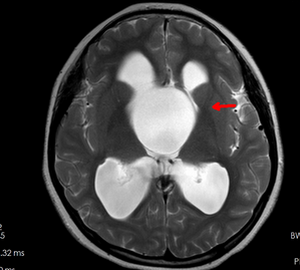

芳芳(化名)今年14岁,正值花季年龄的她却有着自己的烦恼。原来芳芳的生长发育跟同龄人相比明显迟缓,不但个头低于同龄人,并且有喝水多、上厕所频繁的现象,因此也变得不愿与人交流。家人不敢掉以轻心给女儿查了个头部的磁共振。不查不知道,这一查居然发现芳芳脑子正中间的位置有一个巨大“水球”,医学上叫做“鞍上池蛛网膜囊肿”,正是这个大水球压迫丘脑等重要结构引起了芳芳发育慢、尿崩等症状。当地医院条件有限,于是转入郑州大学五附院神经外科三病区就诊。付旭东主任带领其团队认真研究了患者的影像学资料,制定了神经内镜造瘘打开蛛网膜囊肿侧壁,把“死水”变成“活水”的手术方案。手术过程很顺利,术后喝水多、小便频繁的症状明显改善。由于神经内镜创伤很小,芳芳术后很快康复出院。

术前鞍上池巨大蛛网膜囊肿及其典型的“米老鼠”征